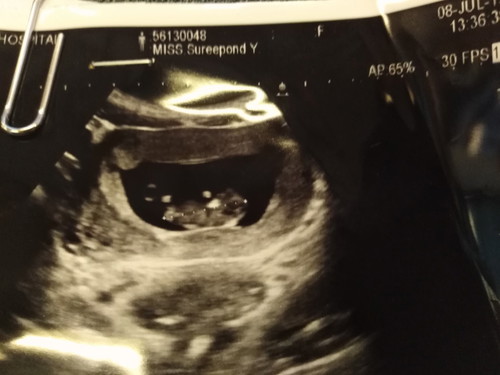

อันนี่ซาวด์ตอน8สัปดาห์ตอนนี้17สัปดาห์แล้วจ้า